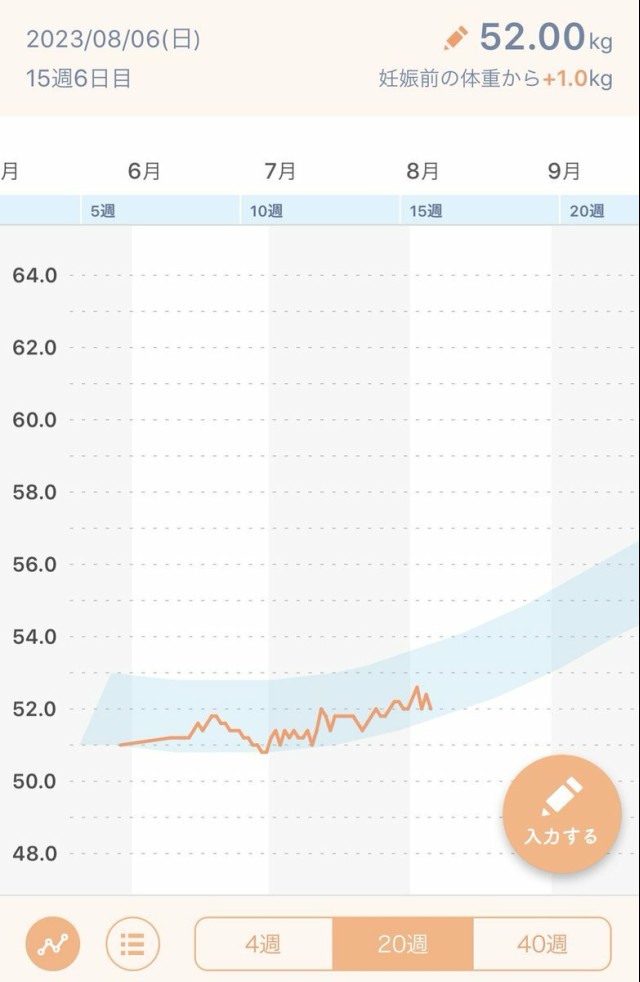

体重管理 ⚠️体重の画像です 妊娠初期も終わりなので体重の記録ᝰ✍︎꙳⋆ 15w頃がつわおわでした??体重が面白いくらいつわりと比例してる? 最初は食べづわりだったのに、途中から食べれる物が限られて(お米?)15w~は何でも食べれるようになって爆食? 中期は積極的に運動するぞ??♀️??♀️⸝⸝꙳